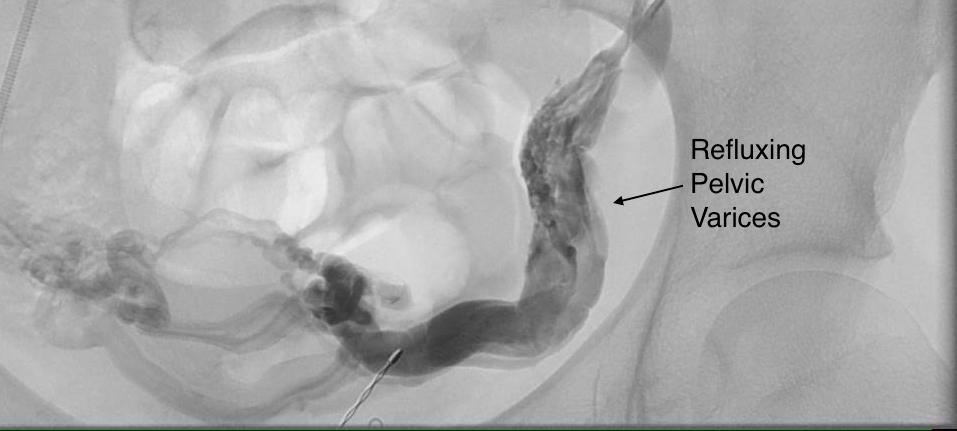

Venogram13

The injection from the LRV showed severe compression of the LRV with a channel only slightly larger than the sheath and avid reflux into the gonadal vein. Selective access into the gonadal vein and venography from a confluence in the pelvis showed that flow was one way from the LRV into the gonadal vein and this filled a large region of pelvic varices.

Venogram19

Venogram23

The gonadal vein was large caliber and refluxed into two large veins in the pelvis. The one that fed the varices was not selected for transposition, but rather the longer straighter tributary. A catheter was left for easier identification during the dissection.